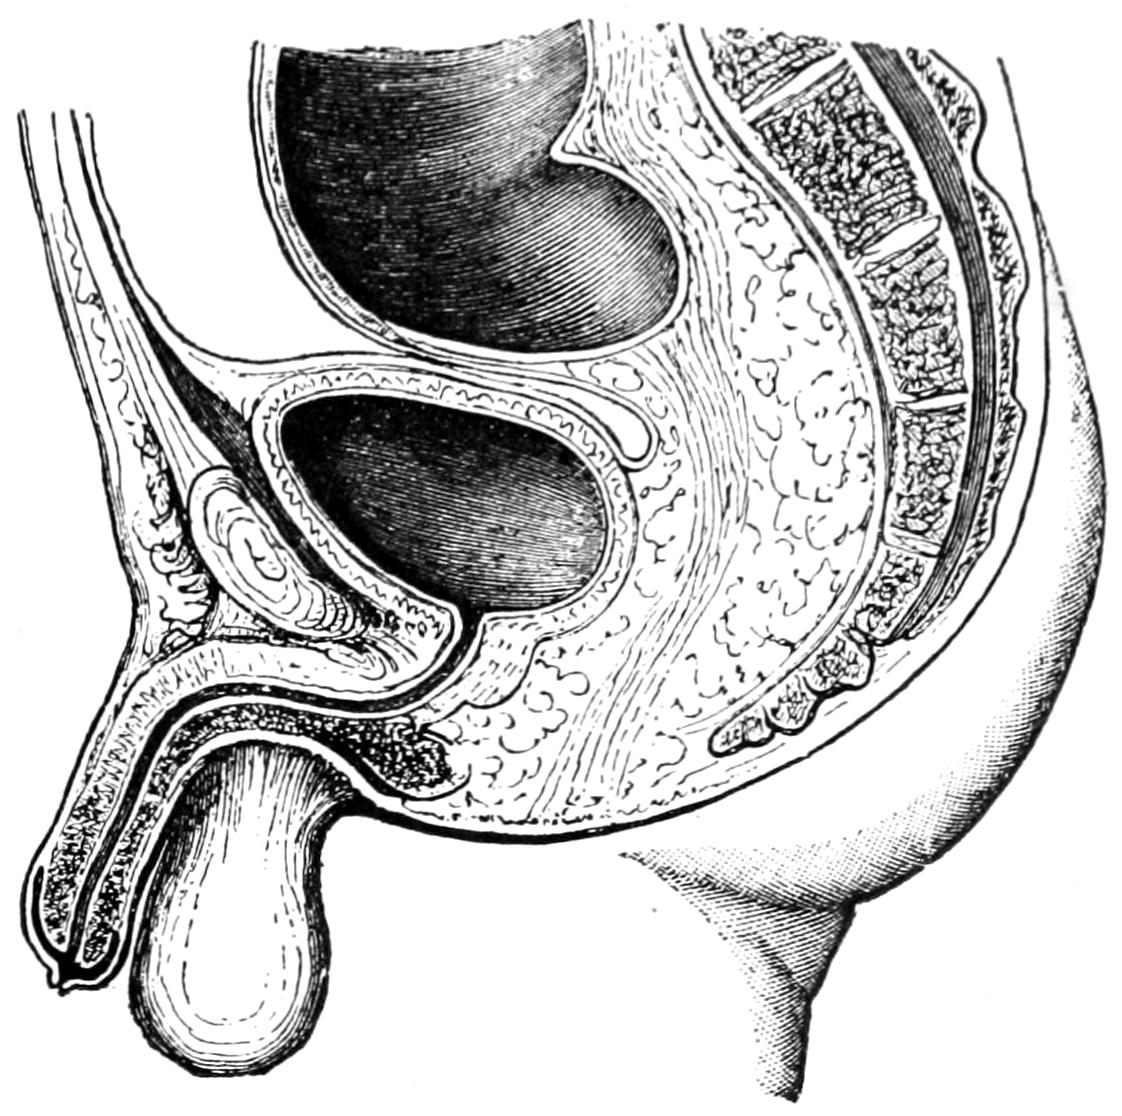

THE BLADDER AND PROSTATE 977